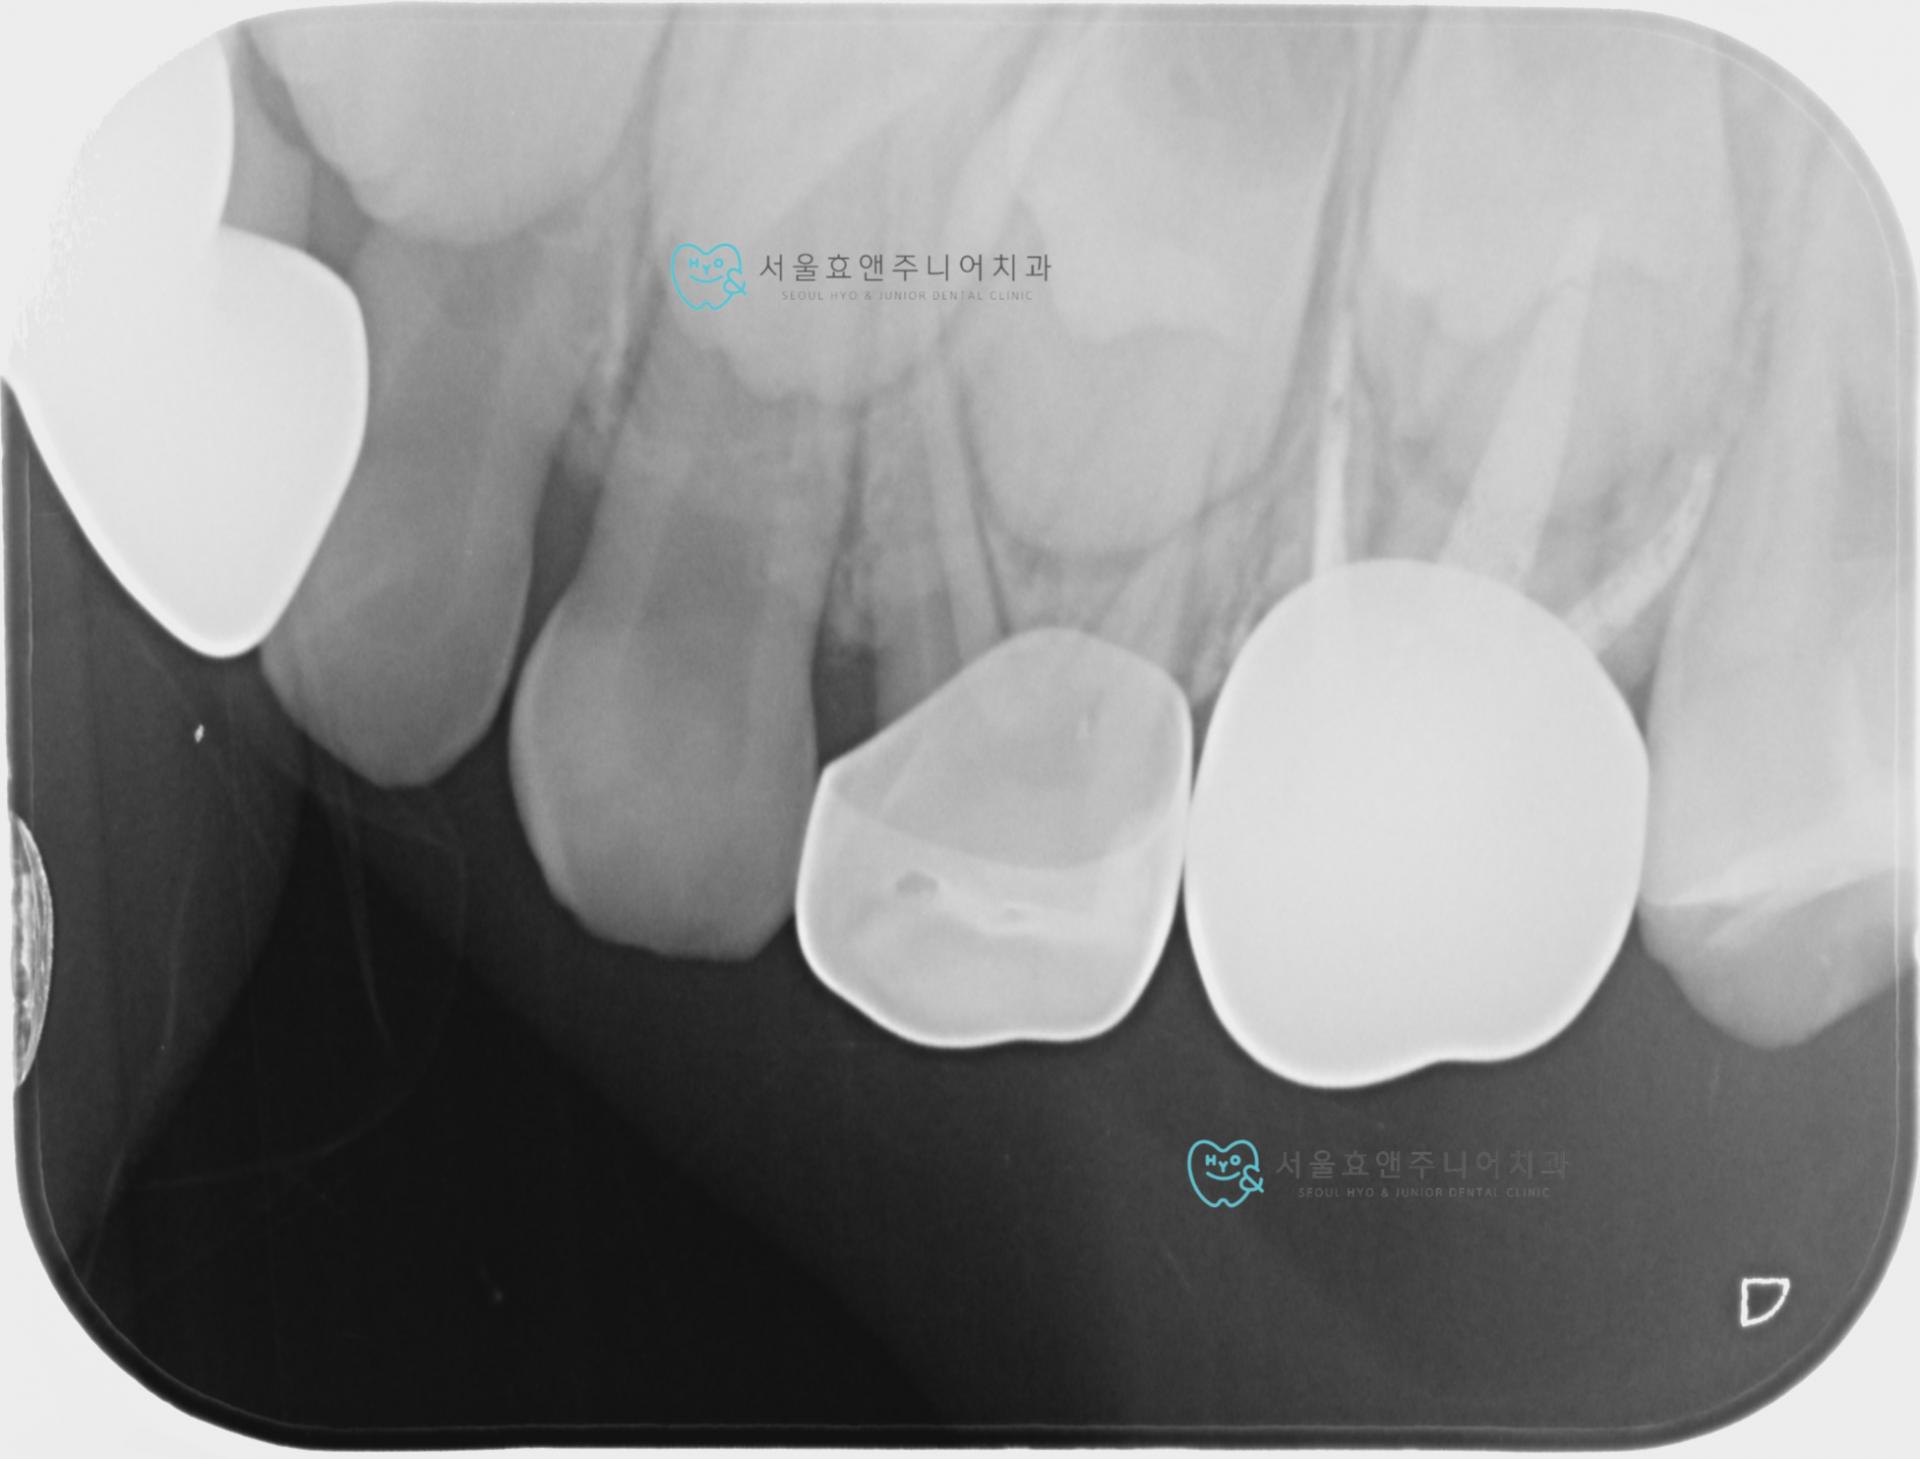

유치크라운_ 찢어진 크라운을 벗겨내고 구멍이 나거나 마모되지 않는 지르코니아 크라운으로 교체

이번에는 구멍나거나 찢어지지 않는 튼튼하고 색깔도 예쁜 치아색 유치크라운으로 바꿔줬으니 유치가 탈락할때까지 다시 씌우는 일 없이 잘 쓰겠죠?^^

유치크라운을 벗겨내자 안에 보이는 심하게 썩은 충치